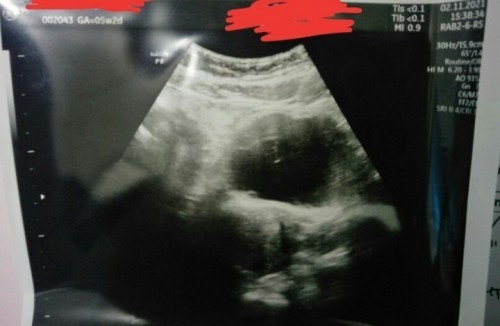

Hasil tespek negatif . UDG usia kehamilan 5week tapi masih penebalan dinding rahim

Bunda mau tanya dong . Saya hpht 26 september.. Haid tggl 27-29 oktober (3hr) awalnya flek coklat lalu agak deras warna merah muda (Tanpa gumpalan) sebelum dan selama haid aku keram perut bawah bagian kanan . Dan hasil tespek negatif Yg di rasa .. Mual , pusing tp ga muntah , sekarang perut bawah agak begah .. Bawaan pengen tidur mulu .. Trus klw mau tidur atau sehabis tidur suhu basal naik Kadang kyk keram2 kyk ada yg bergerak d dalam trus hilang ..sering kentut .. Klw duduk agak lama suka sakit pinggang nya bun. Knpa ya bun . Di usg masih penebalan rahim kata dokternya #seriusnanya #bantusharing #ingintahu #pleasehelp #firstbaby

Penebalan dinding rahim usia 4week

Bun mau tanya .. Aku TP negatif .. Terus aku coba USG karna aku mengalami tanda2 kehamilan . Pusing , mual tp ga muntah , mudah lelah, nafsu makan berkurang, suhu basal saat istirahat meningkat, payudara nyeri , pembuluh darah pada payudara agak kelihatan biru2 dan puting agak menonjol. kemarin aku usg katanya penebalan dinding rahim.. Hpht 17 juli (4week) . Normal kah bun? Soalnya aku TP negatif bun. Dan d anjur kan usg kembali 2 minggu kemudian #seriusnanya #bantusharing #ingintahu #firstbaby #pregnancy